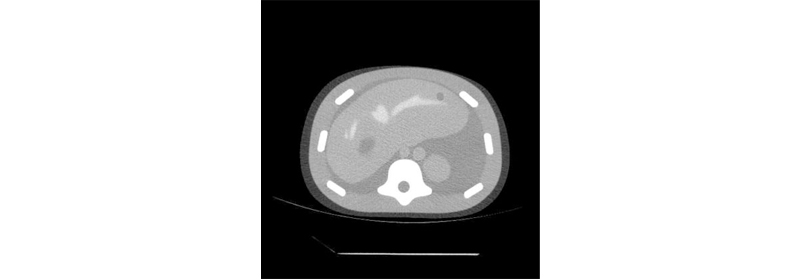

| 內(nèi)部器官 |

肝臟6個病灶(每個小,中,大2個)(2)腎臟(每個中等病變1個)

(1)脊柱

(1)部分肺

(1)門靜脈

(1)腔靜脈

(1)主動脈

(6)肋骨

周圍軟組織(2個大病灶)

| 可選 | 型號035: CT DICOM數(shù)據(jù)集(序列號特定,1.5 mm切片厚度,120 kpv |